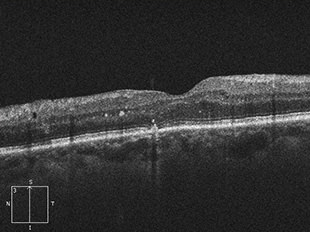

加齢黄斑変性

加齢黄斑変性とは、網膜のほぼ中心部分にあたる特に視機能において重要な部位である黄斑部に、年齢的な変化・変性が生じて起こる病気です。加齢と名のつく通り年配者に多く、近年患者数が急増しており、欧米では失明原因の上位にあげられています。

ものを見る上で特に重要な役割を担う黄斑に障害が起こるため、視野の中心が見えにくい、暗く見える、ものが歪んで見える等、視覚上に症状が出ます。また起こる視力低下の度合いはまちまちですが、矯正視力でも0.1以下という高度の視力障害が起きることもあります。

治療前

治療後

治療前 OCT

治療後 OCT